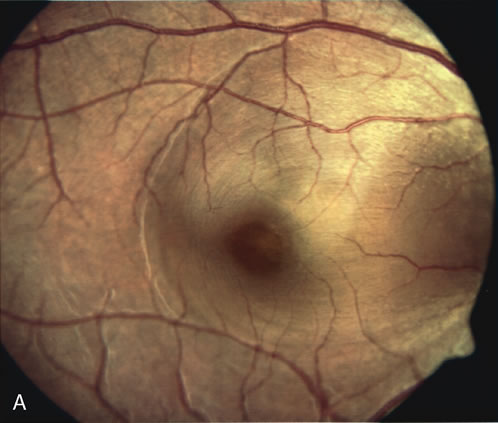

Age-related macular degeneration (AMD) may be divided into two types. Nonexudative (“dry”) AMD has several morphologic forms, including “hard” discrete drusen, shallow retinal pigment epithelial detachments associated with thickened Bruch's membrane (“soft” drusen), and geographic atrophy (GA) of the retinal pigment epithelium (RPE).3 On FA the area of GA appears hyperfluorescent for window defect from the early frames of the angiogram, with late staining of the underlying sclera (Fig. 1). However, these pathologic changes can usually be assessed by clinical examination, and FA is generally not necessary to diagnose nonexudative AMD. An exception is cuticular drusen, which may appear clinically as a subtle disturbance of the RPE; FA reveals multitudes of small, discrete drusen described as “stars in the sky” (Fig. 2). The second type of AMD, which is associated with soft drusen, is known as exudative (“wet”) AMD. It is due to a choroidal neovascular membrane that has incompetent vessels resulting in detachments of the RPE and the neurosensory retina. Consequently, in patients with a large RPE and/or serous neurosensory detachment, FA is often necessary to rule out a choroidal neovascularization (CNV). In general, a small pigment epithelium detachment (PED) and a larger neurosensory detachment overlie CNV, while the opposite is generally the case in a nonexudative PED. Additionally, CNV often presents as a “notched” PED (Fig. 3).4 The presence of subretinal blood or pigment at the border of a PED strongly indicates that the detachment is exudative in origin (Fig. 4). Similarly, a rip in the RPE generally reflects subretinal fibrosis from a CNV (Fig. 5 and 6). The diagnosis is more difficult in patients who have a chronic, organized PED. Such a lesion may be due to either nonexudative AMD or to an organized, fibrotic CNV. Clinically and angiographically, it may be impossible to distinguish between these two conditions. In most cases, however, FA does assist in making the diagnosis.

Fig. 1. Late-phase fluorescein angiography of an eye with a central area of geographic atrophy, which appears hyperfluorescent. A few soft drusen are also present.